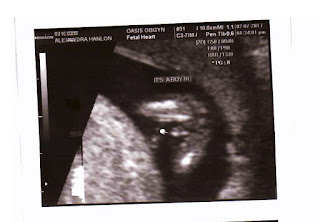

Today we had our anatomy scan and got to see my little hunk again<3 I love him! Just love love love him! I don't think there are words to even describe how happy we are with today's confirmation! Our 13 week scan looked like a definite boy, however I've read online that girls can look like boys during those first weeks of development. Here is a photo from our 13 week scan!

& here are some photos from today's scans with our gender reveal photos :)